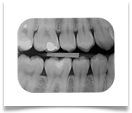

Nel nostro Studio impieghiamo un sistema radiografico computerizzato, il Vista Scan Plus della Dürr che consente di ottenere immagini di alta qualità (vedi confronto analogico/digitale) con dosi radiogene sensibilmente più basse per il paziente.

Con Vistascan Plus siamo in grado di ottenere, nel giro di pochi minuti, tutte le immagini che ci servono per un corretto ausilio diagnostico: bitewing, endorali, ortopantomografie, teleradiografie.